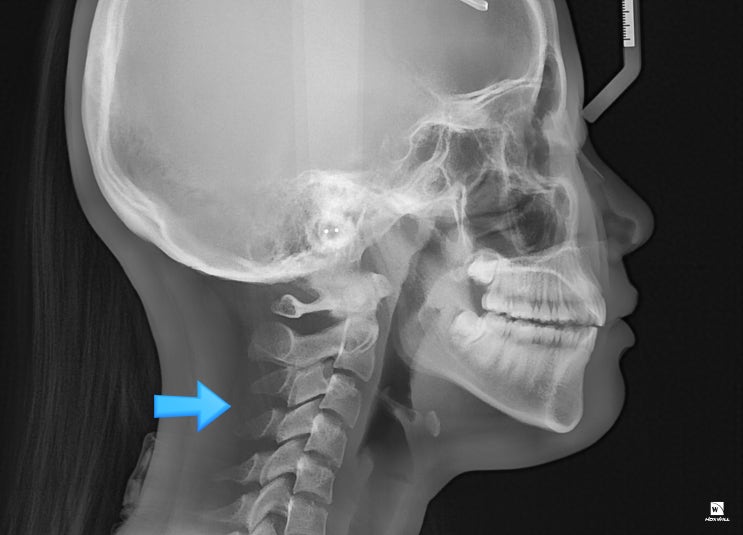

항상 볼쪽이 조이는 느낌이 들고,

1주일 전부터 왼쪽 턱이 아파요.